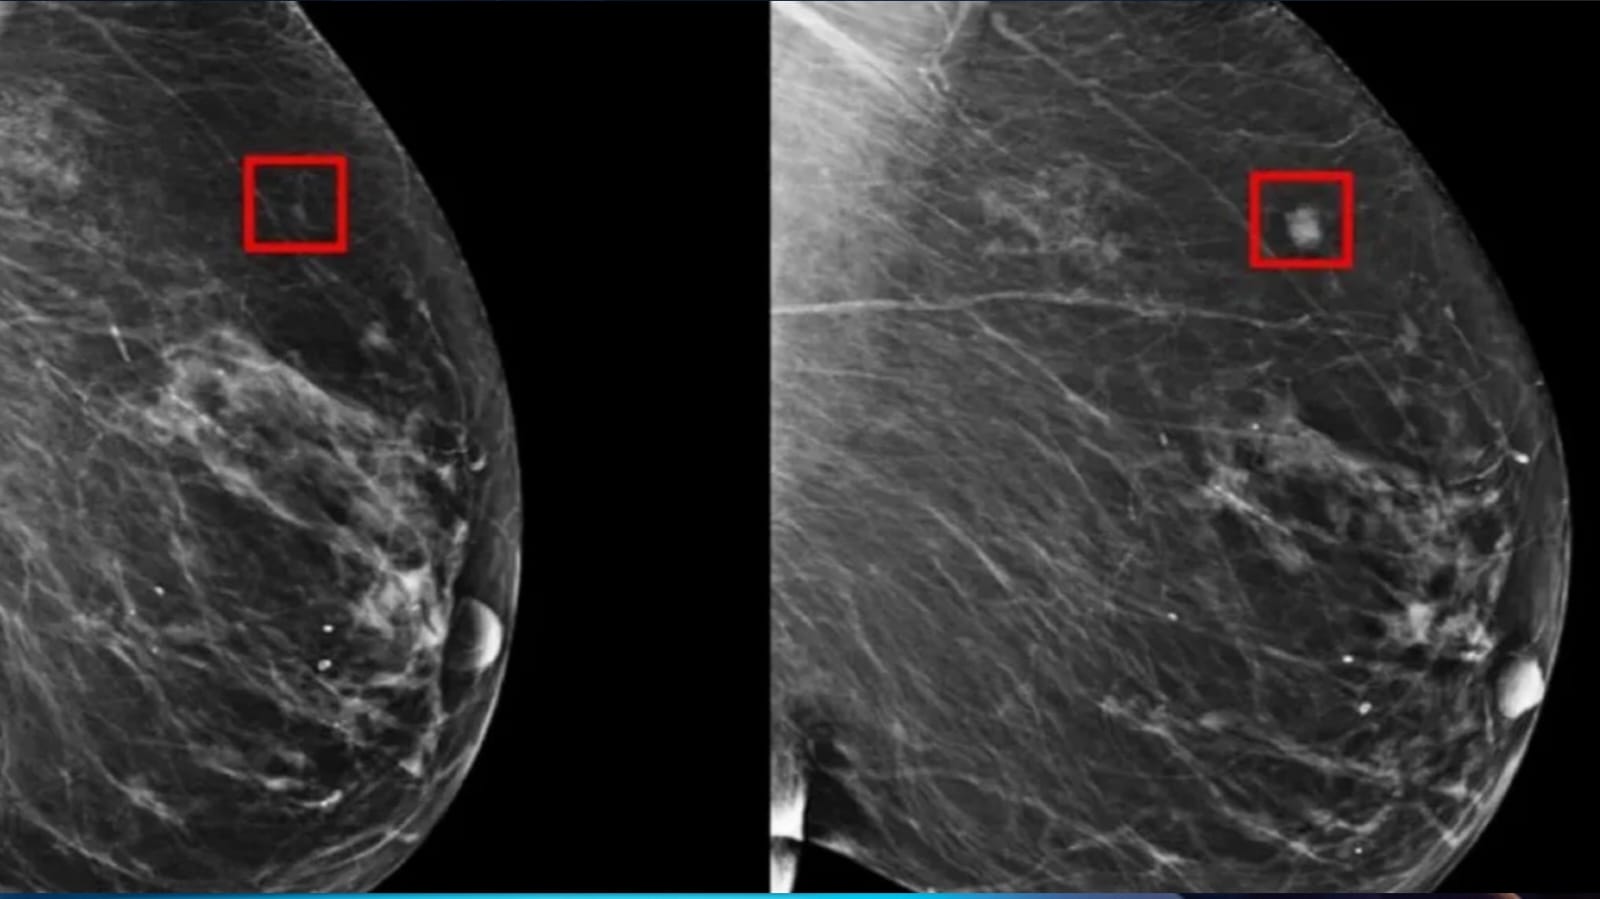

أظهرت دراسة حديثة أن الذكاء الاصطناعي يتفوق على الأطباء في اكتشاف حالات سرطان الثدي خلال عمليات التصوير بالأشعة. الدراسة، التي نُشرت في مجلة “The Lancet Oncology”، بينت أن الذكاء الاصطناعي تمكن من اكتشاف السرطان بنسبة 20% أكثر مقارنة بأخصائيي الأشعة.

حللت الدراسة فحوصات 80 ألف امرأة سويدية معرضة لخطر وراثي معتدل للإصابة بسرطان الثدي، حيث خضعت لتصوير الثدي بالأشعة السينية بين أبريل 2021 ويوليو 2022. قُسمت الفحوصات إلى مجموعتين: المجموعة الأولى تم تحليلها باستخدام الذكاء الاصطناعي وأخصائيي الأشعة لمضاعفة النتائج، بينما قُرأت المجموعة الثانية بواسطة أخصائيي الأشعة فقط. أظهرت النتائج أن الذكاء الاصطناعي اكتشف السرطان في 6 من كل 1000 عملية مسح، بينما اكتشف أطباء الأشعة السرطان في 5 من كل 1000 عملية مسح.